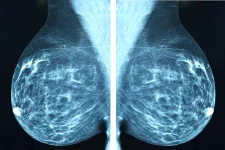

AI support in breast cancer screening: Fewer missed cancer cases

There were fewer cases of breast cancer between two screening rounds, and of the cancers that did develop, fewer were advanced or aggressive. The final results from Lund University...